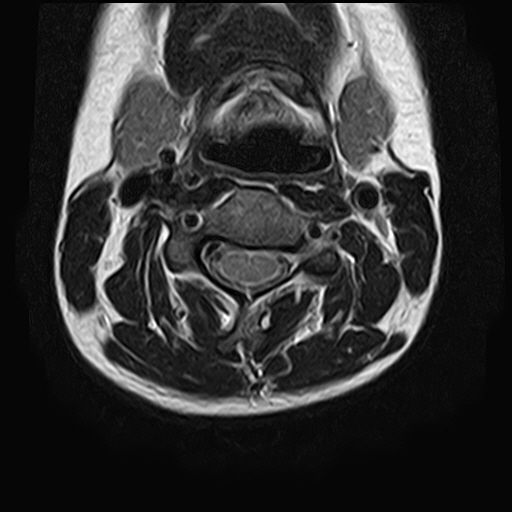

• 1번 째 사진

• 2번 째 사진

• 3번 째 사진

• 4번 째 사진

• 5번 째 사진